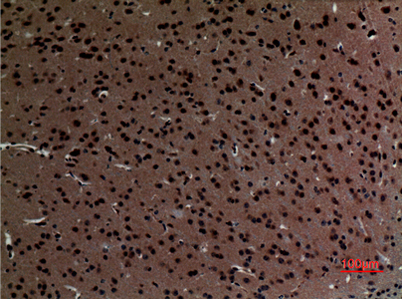

Immunohistochemical analysis of paraffin-embedded mouse-brain, antibody was diluted at 1:100